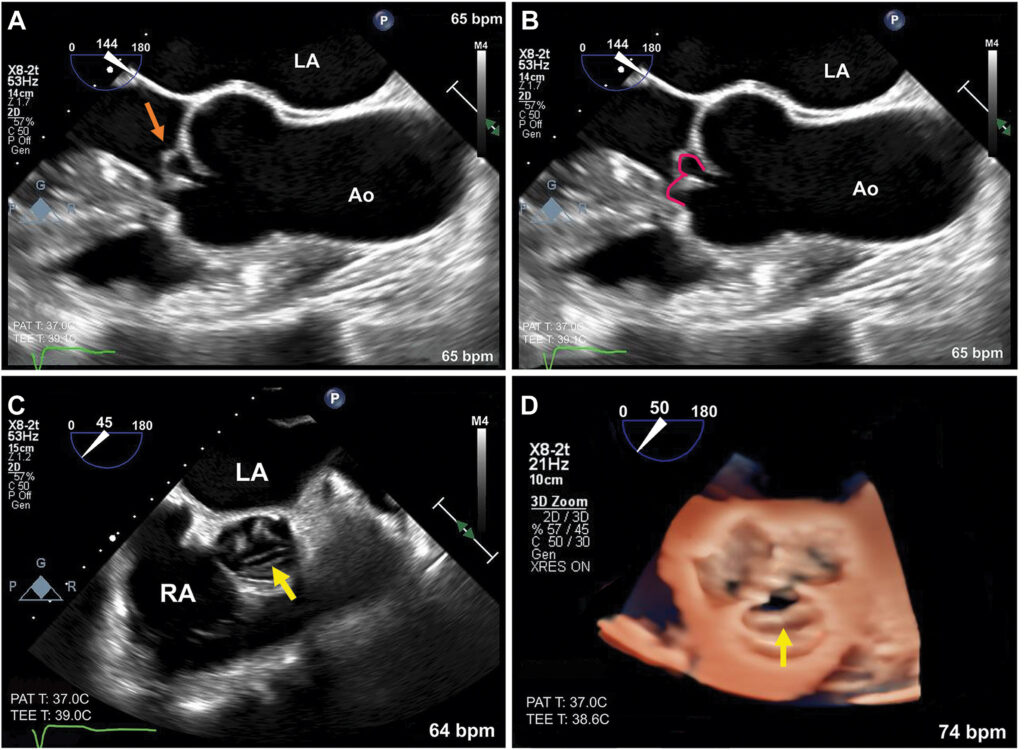

Ecocardiograma transesofágico, realizado para confirmar o mecanismo da regurgitação aórtica, mostrou uma valva aórtica trivalvular com uma dobra transversa no folheto coronariano direito causando prolapso distal.

A IAo importante foi confirmada: volume regurgitante 76 mL, fração regurgitante de 61%, fluxo reverso holodiastólico em aorta abdominal, “flutter” (ver foto) no folheto anterior da valva mitral causando restrição de mobilidade.

O sinal em “W” pode ser observado, ao estudo transesofágico no eixo longo, com a análise em 3D caracterizando a dobra transversa. Este sinal se caracteriza por um formato em W do segmento prolapsado do folheto coronariano direito.